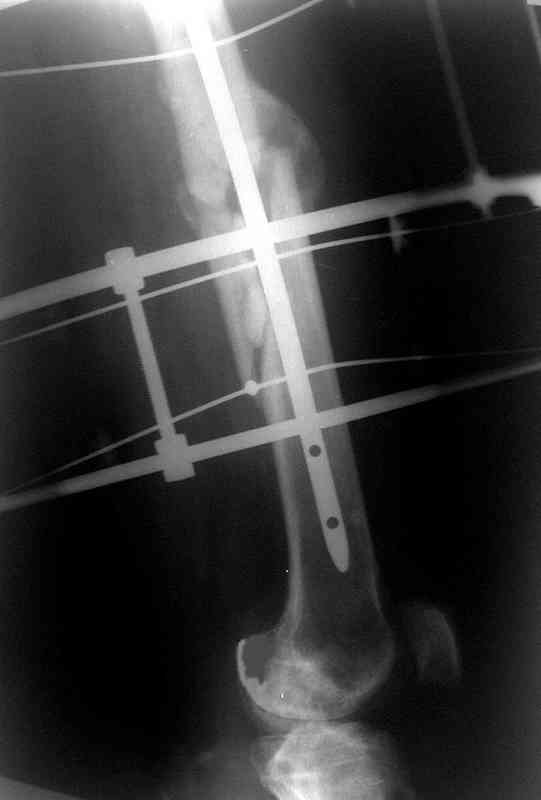

Больной А., 28 лет, поступил в НИИ им. Н.В. Склифосовского 22.12.99 после падения на улице. Жалобы на боли в области левого тазобедренного сустава и левом бедре. Из анамнеза следовало, что 20.06 во время прыжка с парашютом у него возник закрытый оскольчатый перелом средней трети левой бедренной кости со смещением отломков, по поводу чего в одной из ЦРБ Московской области через 3 дня после травмы был произведен открытый интрамедуллярный остеосинтез штифтом типа Кюнчера.

по его наружной поверхности послеоперационный рубец - рана зажила первичным натяжением. При измерении длины бедер обнаружено укорочение левого бедра на 4,5 см. На рентгенограммах этого бедра: ось конечности правильная, отмечается захождение основных костных фрагментов по длине, проксимальный конец штифта выступает слишком медиально и высоко относительно большого вертела, периостальная мозоль незначительна.22.12 - через 6 месяцев после операции, произведенной в ЦРБ, нами по поводу замедленно консолидирующего перелома левой бедренной кости с ее абсолютным укорочением под наркозом произведена операция: удаление штифта, закрытый блокирующий интрамедуллярный остеосинтез перелома левого бедра штифтом без рассверливания (UFN) длиной 40 см, диаметром 10 мм с блокированием только проксимальных отверстий (динамический остеосинтез). Наложен аппарат Илизарова на 4 полукольцах с целью удлинения укороченного бедра. Послеоперационное течение без особенностей. Ежедневно осуществляли дистракцию отломков на 1 мм. Через 3 недели после операции больной выпи-сан на амбулаторное лечение с продолжением дистракции отломков. В течение 1,5